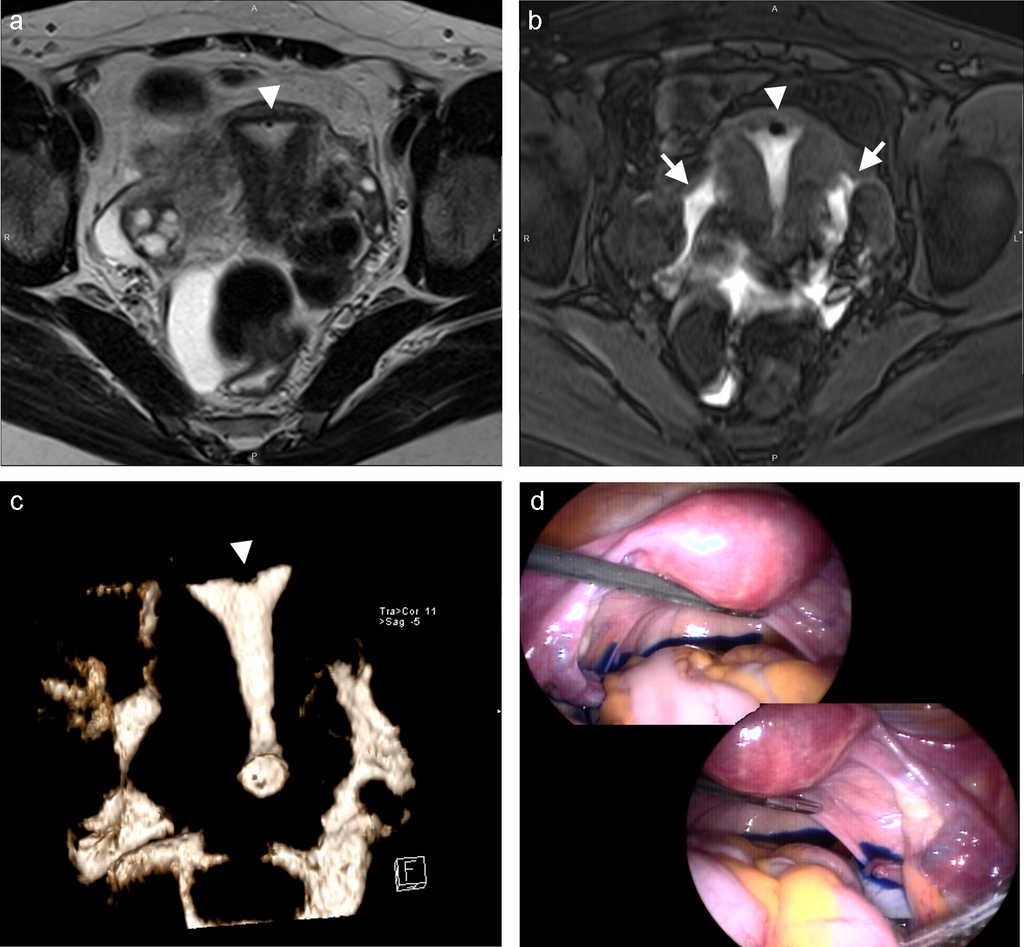

Con la paciente bajo anestesia general, y tras la inserción de los trocares y la cámara laparoscópica, se colocó el manipulador uterino desechable, VCare (ConMed, Utica, Nueva York). A través del dispositivo, se inyectaron 10-20 ml de azul de metileno en la cavidad uterina para confirmar el derrame del colorante en la cavidad pélvica y, por lo tanto, comprobar la permeabilidad tubaria (fig. 1). Los datos fueron tabulados.

Nuestros resultados iniciales en el rendimiento diagnóstico de la HSG-RM para la evaluación de la permeabilidad tubaria han demostrado una alta sensibilidad y especificidad en comparación con el verdadero método de referencia para esta evaluación, la laparoscopia con cromotubación (figs. 1 y 3). Aun cuando se consideró cada trompa de Falopio por separado, y pese a no poder visualizar en algunas pacientes el contorno mismo de la trompa, se observó una alta sensibilidad y especificidad para la trompa izquierda y una alta especificidad para la derecha. La causa de la baja sensibilidad observada en esta última aún se desconoce y amerita más investigaciones con una muestra poblacional más grande.